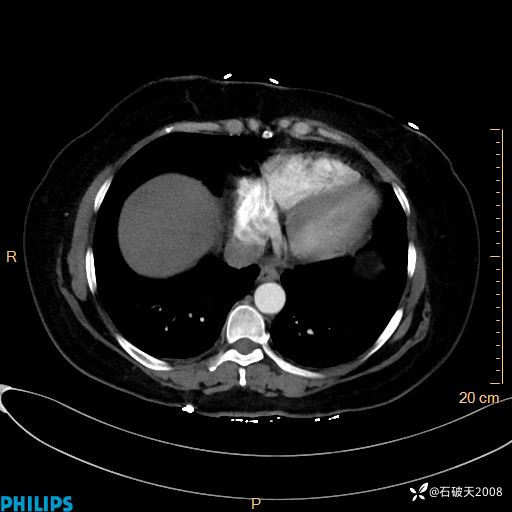

静脉期